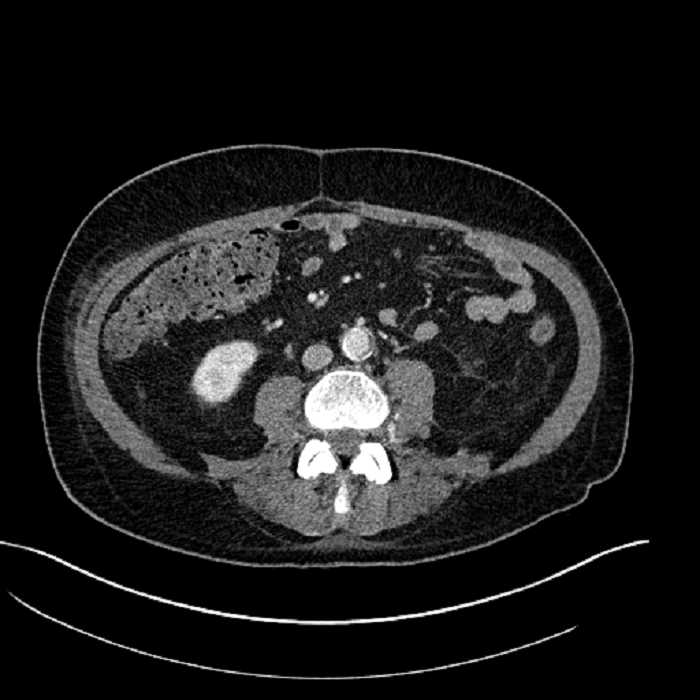

Age: 63

Sex: Male

Indication: Abdominal pain

• Large fluid density structure in hepatic segments 7 and 8 measuring 10 x 7 x 7 cm with internal septation and circumferential ill-defined low density compatible with edema

• Peripherally enhancing subcapsular collections along the anterior margin of the left hepatic lobe measuring 3 x 1 cm and 2 x 1 cm

• Clearly marginated fluid density structure in segment 7 and several other scattered tiny hypodensities, which likely represent cysts

• Hepatic abscess

Acute sigmoid diverticulitis complicated by a small contained perforation and a large abscess in the right hepatic lobe. Additional small subcapsular abscesses along the anterior margin of the left hepatic lobe.

• The classic CT imaging appearance is a double target sign with internal low density surrounded by an internal enhancing rim (capsule) and a low density external rim (edema)

Hepatic abscess showing the double target sign with low density internally surrounded by a thin inner enhancing rim (red arrow) and ill-defined outer low density rim (yellow arrow). Blue arrow indicates an internal septation. Red arrows: additional smaller subcapsular abscesses. Red arrow: focal contained perforation associated with diverticulitis.